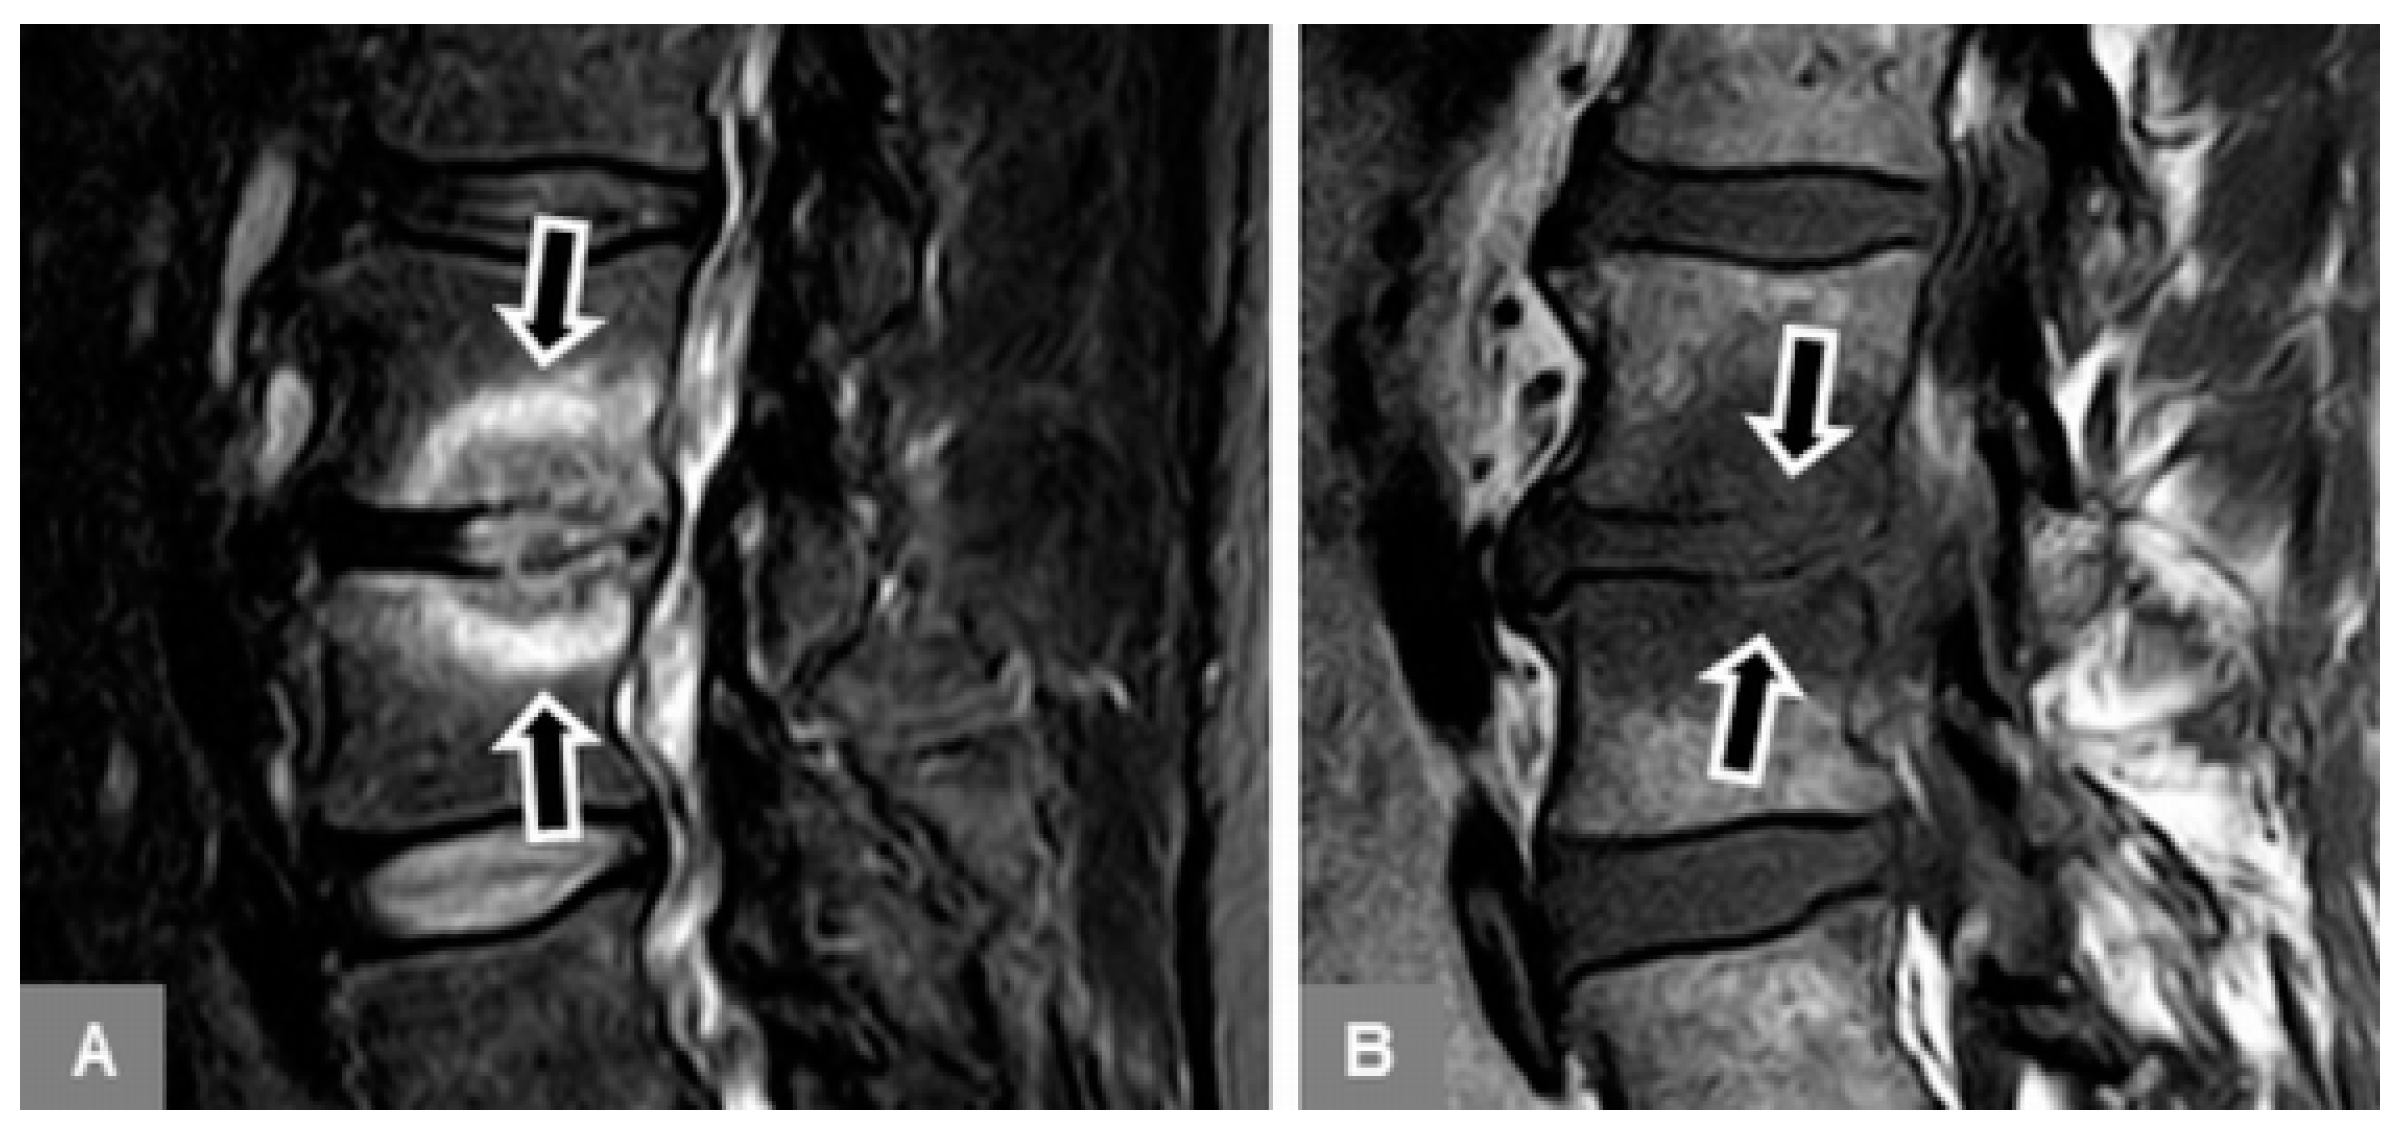

3.1. Bone Marrow Edema Extent, T1-w Signal Ratios of Edema to Unaffected Bone, and Visual T1-w Signal Assessment

3.2. Vertebral Endplate Contour